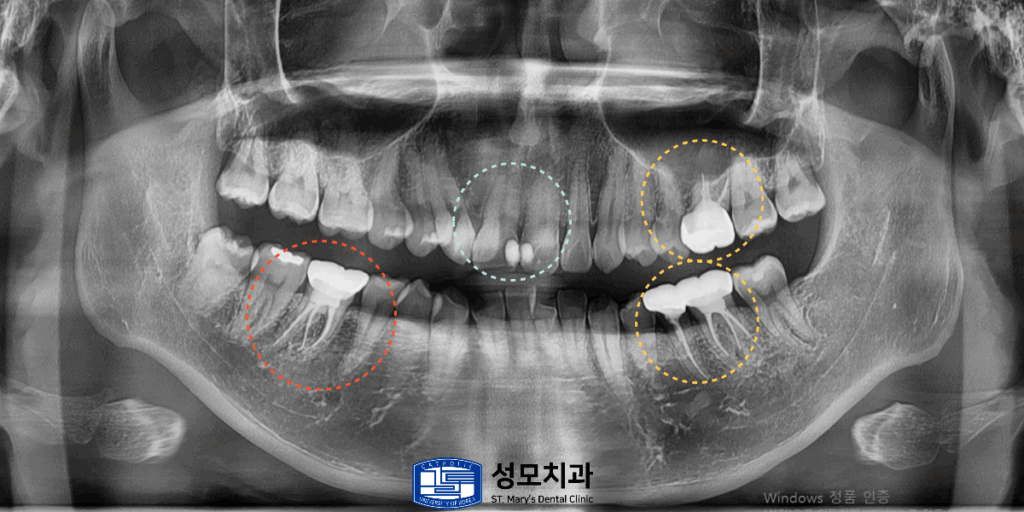

2. 치료 전 파노라마 사진

빨간색으로 표시된 오른쪽 아래 어금니에는

아말감 주변의 치질이 파절되거나 벌어져 있어서

2차 우식이 진행된 치아가 있었습니다.

3. 치료 계획 수립

왼쪽 위아래에서는 내부 코어까지만 형성된 상태로

최종 보철이 미완성인 치아 두 개가 확인되었는데요.

노란색으로 표시된 부분은 충치가 깊게 진행되어

치관이 약 3분의 1만 남아있었습니다.

파란색으로 표시된 상악 전치부 첫 번째 앞니의

사이 인접면에는 초기 우식과 변색이 동반되어 있었습니다.